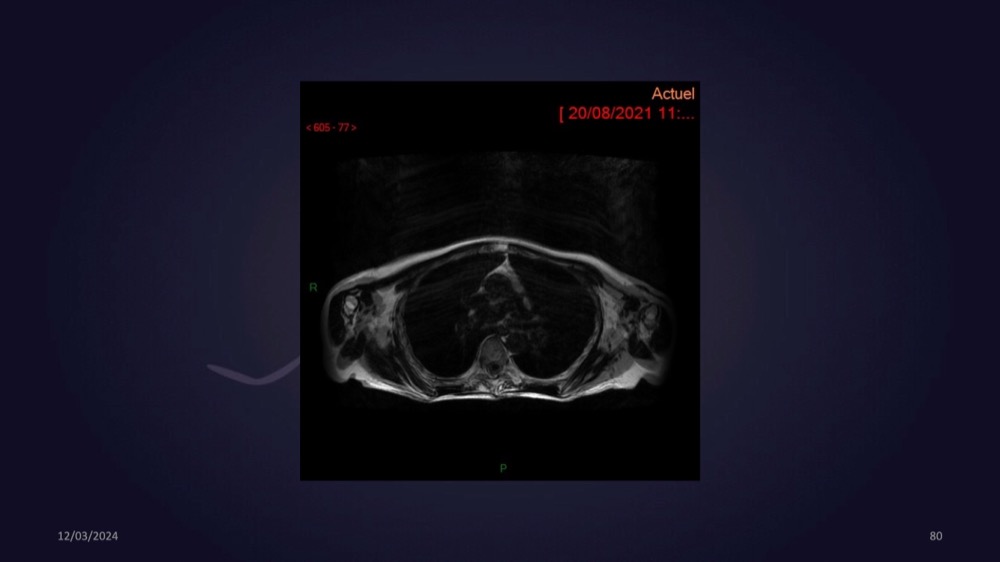

Mezhgani / Dimitri Boulos / Carlier 23/03/2022